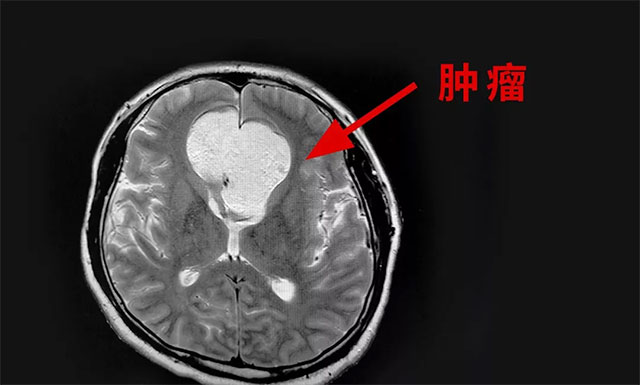

▲ 影像显示肿瘤有拳头大小

头颅磁共振检查显示,额部(中线处)见团状异常信号灶,矢横高径约5.8*5.5*5.4cm,周围脑实质受压移位,肿块向鞍内生长。